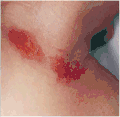

Symptoms of a prior nuchal cord shortly after birth in the baby may include duskiness of face, facial petechia, and bleeding in the whites of the eye.[1] Complications can include meconium, respiratory disease, anemia, and still birth.[1]

Petechiae and subconjunctival bleeding due to tight nuchal cord -

Petechiae on face due to tight nuchal cord -

Facial duskiness due to tight nuchal cord -

Abrasion from a nuchal cord